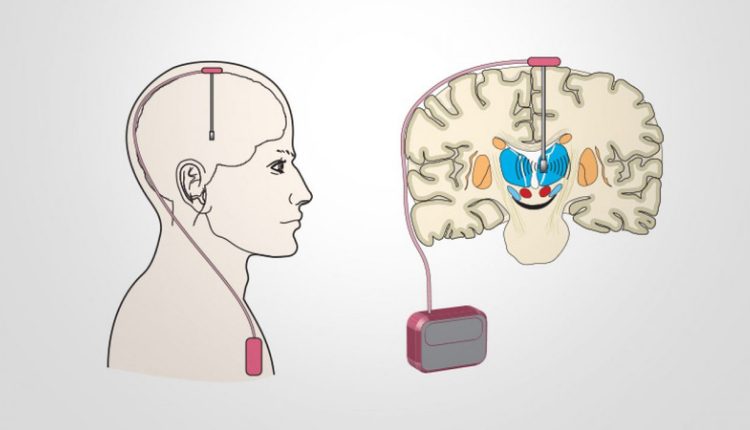

تحفيز العصب المبهم بدلا من الجراحة

- VNS (تحفيز العصب المبهم) هو أحد الأساليب العلاجية المصممة لمنع النوبات.

- وذلك عن طريق إرسال نبضات كهربائية معتدلة ومنتظمة إلى الدماغ عن طريق تحفيز العصب المبهم.

- يتم إجراء VNS عن طريق زرع جهاز صغير جراحي يشبه جهاز تنظيم ضربات القلب الذي يحفز العصب المبهم vagus nerve على إرسال إشارات إلى الدماغ.

- يمكن أن تقلل هذه الإشارات من نشاط النوبات أو حتى أنها قد تقضي عليها.

- وعادة ما يتم وضعها عند الأشخاص الذين يستجيبون بشكل سيئ لأدوية النوبات.